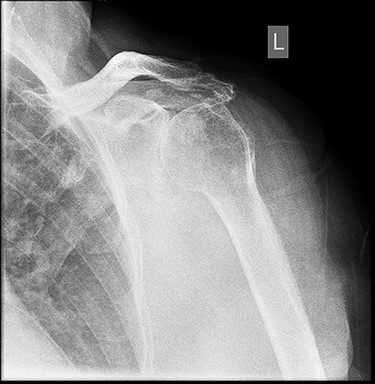

X-ray imaging showed degenerative changes in the glenohumeral and acromioclavicular articulations.

X-ray imaging showed degenerative changes in the glenohumeral and acromioclavicular articulations with inferior displacement of the humeral head.